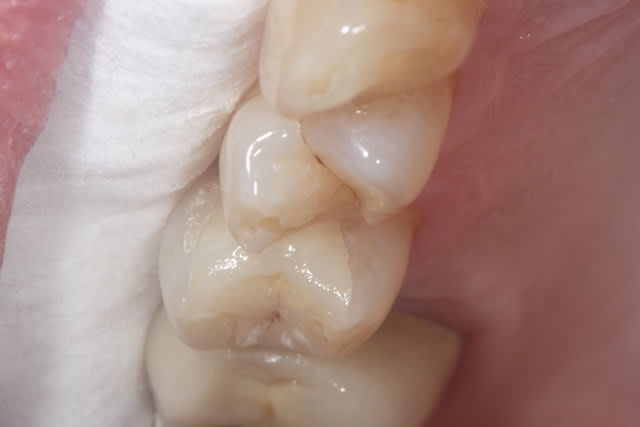

Puisque tout le monde montre des photos, à mon tour.

Il m'aura quand même fallu un petit moment avant de réussir à faire des onlay qui ressemble à quelque chose... Comme quoi, c'est pas que le prothésiste qui bosse!

Par contre me former ça commence à me coûter cher... Je ne fait presque plus de SPR50/SPR57...